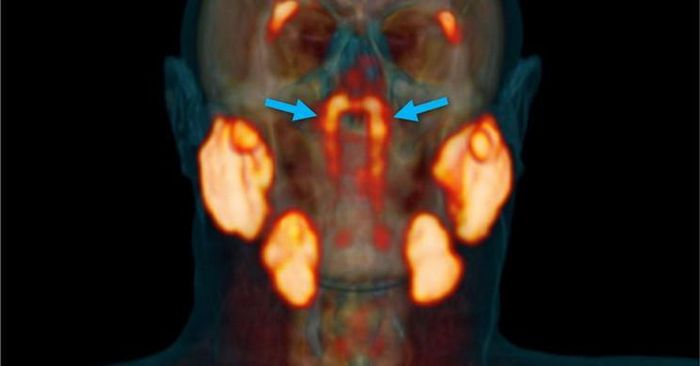

Vào tháng 10/2020, các nhà nghiên cứu đã phát hiện ra rằng con người có một bộ tuyến nước bọt phụ chưa được phát hiện trước đây ngay bên trong đầu của chúng ta.

Hình ảnh trong phát hiện tuyến nước bọt mới vào năm 2020.

Trong phát hiện năm 2020, "thực thể không xác định" đã được phát hiện một cách tình cờ. Một nhóm các nhà khoa học đã nghiên cứu bệnh nhân ung thư tuyến tiền liệt. Họ sử dụng một loại phương pháp chụp hình ảnh tiên tiến gọi là PSMA PET / CT. Và lần này, hình ảnh đã hiện lên một thứ gì đó khác.

Nhà nghiên cứu Wouter Vogel tại Viện Ung thư Hà Lan, giải thích: "Theo những gì chúng ta biết, các tuyến nước bọt hoặc tuyến nhầy duy nhất trong vòm họng có kích thước siêu nhỏ và có tới 1.000 tuyến rải đều khắp niêm mạc. Vì vậy, hãy tưởng tượng sự ngạc nhiên của chúng tôi khi tìm thấy tuyến này."

Cho đến nay, chúng ta đã biết về ba tuyến nước bọt chính: tuyến mang tai, tuyến dưới sụn và tuyến dưới lưỡi. Chúng có một vai trò trong quá trình tiêu hóa thức ăn. Ngoài ra, con người có khoảng 1.000 tuyến nước bọt cực nhỏ trải khắp khoang miệng và đường tiêu hóa. Nhưng chúng quá nhỏ để có thể nhìn thấy bằng mắt thường. Trong khi đó, hệ thống tuyến nước bọt được phát hiện bởi nhóm của Tiến sĩ Vogel lớn hơn nhiều, nó nằm sau mũi, phía trên vòm miệng và gần tâm đầu của chúng ta.

Nhóm nghiên cứu đề xuất rằng vùng này nên được tránh trong quá trình điều trị bức xạ vì các tuyến nước bọt được biết là đặc biệt dễ bị tổn thương do phóng xạ.